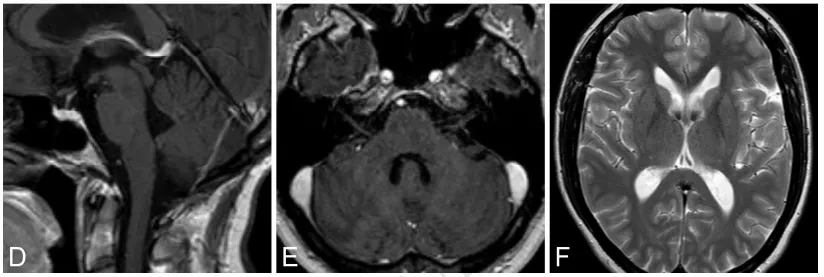

32岁娜娜,因头痛、眩晕及间歇性瞳孔不等大就诊。MRI示第四脑室均匀强化占位并梗阻性脑积水(图2A–C)。

术中在神经电生理监测下全切肿瘤。术后出现短暂右侧外展神经麻(约数日),以及右侧舌咽、舌下神经麻(约两周),均完全恢复。

术后即刻MRI未见肿瘤残留,术后32个月随访MRI未见肿瘤复发及脑积水征象(图2D–F)。